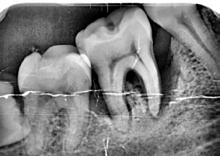

Lâexamen exobuccal Ă©tait sans particularitĂ©s. Lâexamen endobuccal a objectivĂ© une inflammation marginale modĂ©rĂ©e Ă sĂ©vĂšre gĂ©nĂ©ralisĂ©e avec un indice dâOleary Ă 68%, un indice gingival (BoP = Bleeding on Probing) Ă 76%, et un trama occlusal sur 42 (Figure 1). Le bilan parodontal montre des sites avec une profondeur de sondage (PS) de 12mm, et plus de 50% des dents prĂ©sentant une perte dâattache â„ 5mm. Le bilan radiographique a montrĂ© des pertes osseuses terminales, avec un rapport perte osseuse/Ăąge Ă 4,5 (Figure 1)

Figure 4 : (a) Vue clinique Ă 6 mois ; (b) bilan radiographique Ă 3mois (b) ; (c) Retro alvĂ©olaire sur la 46 avant et aprĂšs lambeau dâassainissement